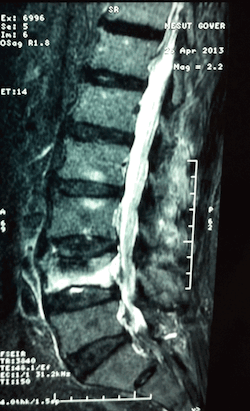

Kemik yoğunluğu azalmış, dolayısı ile yüklenme ile kırık riski taşıyan veya kırılmış olan omurgaların veya kanser metastazlarına bağlı omurga gövdesindeki yükseklik azalmalarının olduğu durumlarda omurga gövdesi içerisine polimetilakrilat(kemik çimentosu) enjekte edilmesi işlemine vertebroplasti denir. Vertebraplasti omurga içi kemiğin kuvvetlendirilmesine yönelik bir işlemdir.

Hastaya uygulama öncesi sakinleştirci ilaç uygulanır. Hasta yüz üstü pozisyonda ameliyat masasına yatırılır. Omurga kırığının yerine göre sırt veya bel bölgesinde girişimin yapılacağı yer steril olarak silinip örtülür. Skopi(X-ışınları kullanarak görüntüleme sağlayan cihaz) kontrolü ile müdahalenin yapılacağı bölge görüntülenir .Girişim noktası saptandıktan sonra giriş noktasına lokal anestezik uygulanır. Bu noktadan küçük bir kesi yapılarak vertebroplasti iğnesi kemikle temas edene kadar ilerletilir ve iğne döndürülerek omurga korteksinin içine girilir. İğne yerleştirildikten sonra sıra kemik çimentosu skopi kontrolü ile sement verilir